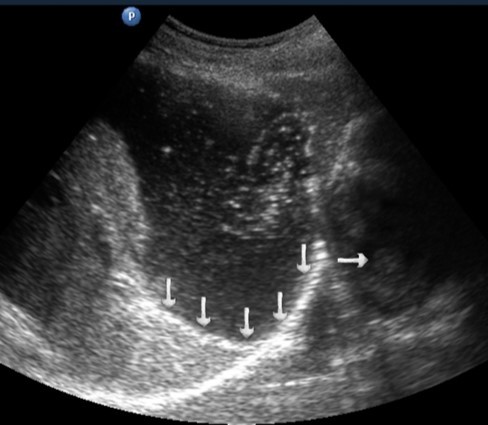

TAS of an empty stomach visualizes only the abdominal part of the esophagus which is 3-4 cm long. In the center of the esophagus, the mucosa of both walls is well defined as a thin hyperechoic linear structure. The walls of the unchanged esophagus have a linear layered structure (Figure 1).

Figure 1.Ultrasonography of the abdominal esophagus (vertical arrows). Horizontal arrow shows mucosa of the esophagus